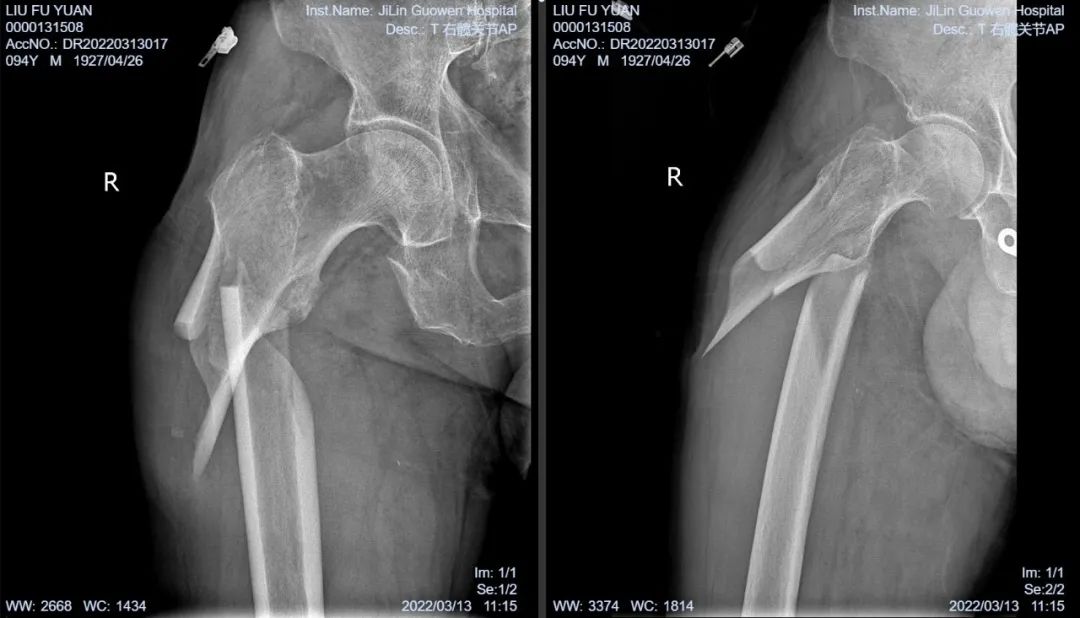

3月13日伴著急促的腳步聲、轆轆的車輪聲,夾雜著患者痛苦的呻吟聲,一位94歲的高齡老人被急診科醫(yī)護人員緊急送至骨科療區(qū)。這是怎么回事?呂國褔主任帶著值班醫(yī)生在做好防護措施后,第一時間來到患者病床前,經(jīng)急診科醫(yī)生診斷告知為 “股骨近端粉碎性骨折”,患者右大腿近端嚴(yán)重畸形,骨折端已經(jīng)刺穿前方肌肉直達(dá)皮下,局部皮膚高高隆起,局部皮膚有挫傷灶,呈青紫色,皮膚變薄,皮膚外可明顯觸及骨折斷端,右股骨X線片示:右股骨近端粉碎性骨折,斷端移位明顯,斷端銳利,近斷端位于前方皮膚下,局部皮膚隆起。患者疼痛劇烈,痛苦難耐,測生命體征:血壓:220/110mmHg。